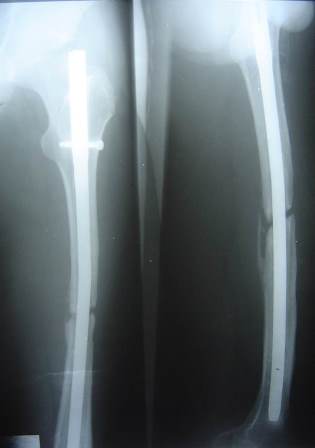

5-year follow-up X-ray